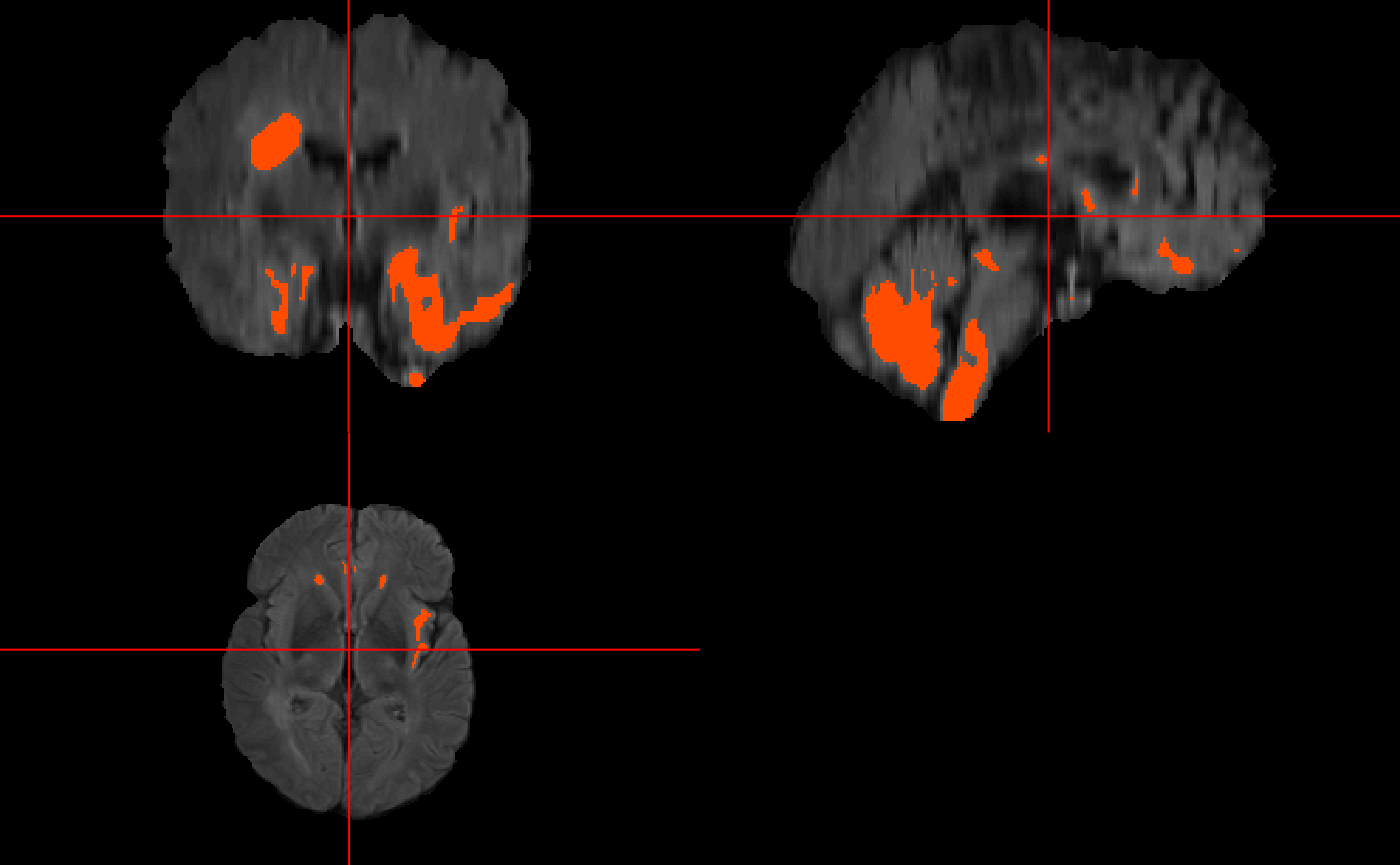

# comparison to ground truth

double_ortho(x = y_img, y = test.preds[[1]] > 0.5,

NA.x = TRUE,

NA.y = TRUE,

xyz = xyz(y_img),

col = "white",

col.y = "white") #binary prediction